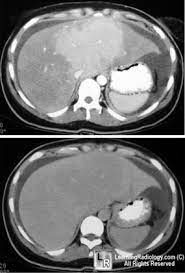

Chiasmata -mə-tə or chiasmas also chiasms 1. Esophageal varices are extremely dilated sub-mucosal veins in the lower third of the esophagus. Located in metro Denver northern Colorado and western Nebraska serving all of the Front Range our team consists of board-certified and fellowship-trained interventional radiologists. This results in hepatic congestion similar to Budd-Chiari syndrome and post-sinusoidal portal hypertension. The patients condition should be monitored throughout the procedure. They are most often a consequence of portal hypertension commonly due to cirrhosis. Toxic injury to liver sinusoids causes sloughing of endothelial cells that embolize to hepatic venules and cause eventual fibrosis of the venules. Coin in the Esophagus. There is no clear consensus regarding the number of occluded veins some authors claim that there should be at least one occluded hepatic vein 7 others state that there are no significant.

Carcinoma of the Colon. Budd-Chiari syndrome a blockage in one or more veins that carry blood from the liver back to the heart. And coumarin skin necrosis adrenal gland hemorrhage and infarction. Toxic injury to liver sinusoids causes sloughing of endothelial cells that embolize to hepatic venules and cause eventual fibrosis of the venules. Chiari malformation CM is a structural defect in the cerebellum characterized by a downward displacement of one or both cerebellar tonsils through the foramen magnum the opening at the base of the skull. Embolism and thrombosis of. La présence dune ou plusieurs affections prothrombotiques est fréquente La prise en charge repose sur un traitement anticoagulant précoce le traitement de l.